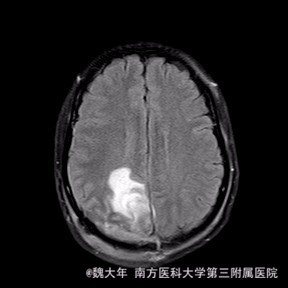

52岁,女性,因“反复头痛10余年,加重1年”入院。患者10余年前无明显诱因始出现头痛,表现为全头发作性胀痛,反复发作,无伴头晕、恶心,无呕吐、肢体抽搐,自行服药(具体不详)及休息后缓解,未予特殊处理。1年前患者觉头痛逐渐加重,以右顶部为甚,劳累或日晒后加重,无头晕、视物旋转,无恶心、呕吐,无发热、寒战,休息或平躺后症状稍有缓解,自行服药不能改善,至当地医院就诊,查颅脑MRI和CT提示“右侧顶部脑膜瘤”。

行“右顶开颅右顶部矢状窦旁脑膜瘤切除术”。取右顶马蹄形手术切口 ,颞侧翻开皮瓣,电刀切开骨膜,中线矢状缝上前、后极各钻一孔,颞侧后方钻一孔,铣刀铣一长方形(7*6cm)骨瓣,见硬膜表面较多点状渗血,予充分止血,悬吊硬膜。 显微镜下切除肿瘤:沿肿瘤边缘剪开硬膜后,见一大小约5*5*6cm肿瘤,沿硬膜内侧面呈匍匐状生长,边界与脑组织有蛛网膜分隔,质地较韧,基底与矢状窦关系密切,靠内侧与大脑镰粘连紧密,血供丰富。仔细分离肿瘤与脑组织的粘连,全切除肿瘤。肿瘤基底与矢窦粘连紧密,并破坏矢状窦侧壁,予低功率电刀反复烧灼,直至肿瘤无明显血供表现。严密止血后常规关颅。

术后1周复查头颅MR未见明显肿瘤残留,拆线后出院。